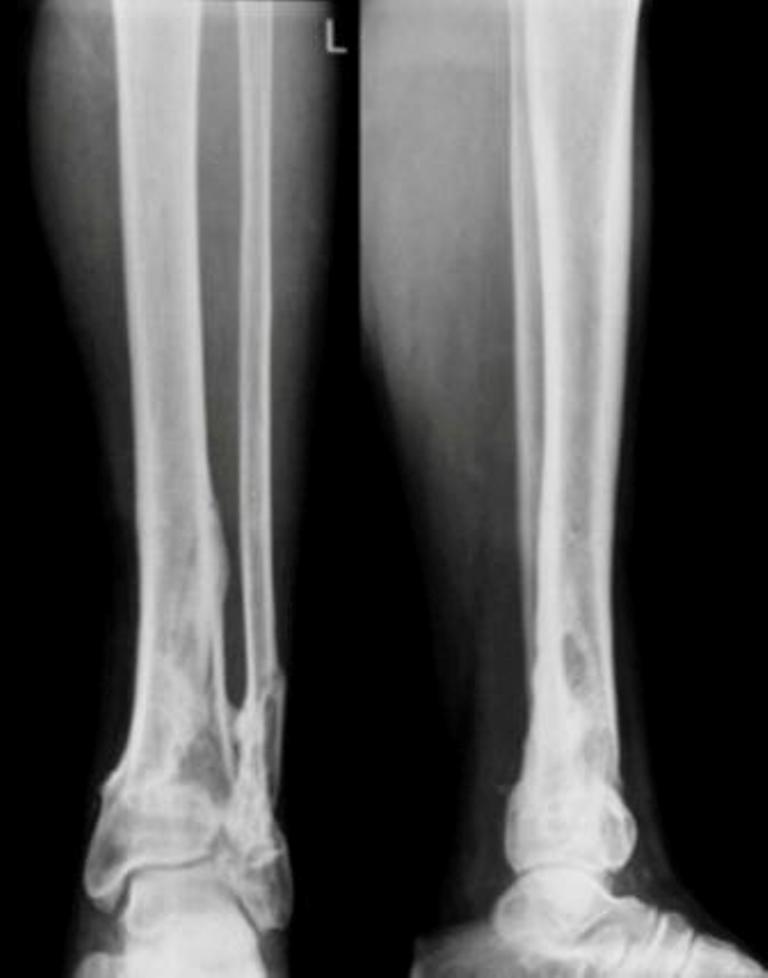

На рентгенограммах – классический перелом пилона (C3). Современный подходы к лечению таких повреждений – двухэтапный протокол. Сначала - дистракционный аппарат (стержневой или спицевой) в течение двух недель. На этом этапе следуют принципу: повреждения мягких тканей – всё, повреждения костей – ничто. Никаких оперативных вмешательств в этот период выполнять не рекомендуется (несмотря на «удовлетворительное состояние» мягких тканей). КТ необходимо выполнять в дистракционном аппарате. Будет более понятная картина, позволяющая спланировать ход последующей открытой репозиции и остеосинтеза. Сдержано относятся к первичному артродезированию. Многое зависит от опыта хирурга и технического оснащения. Ход оперативного вмешательства можно будет обсудить после выполнения рентгенограмм и КТ в дистракционном аппарате. Более информативна КТ со срезами в корональной плоскости. Результат при прочих равных условиях находится в прямой зависимости от точности репозиции суставной поверхности. Долгосрочный прогноз, как правило, плохой. В 60-70% случаев через пять лет всё заканчивается артродезом.

До лечения, в процессе, через 8 мес.

Спасибо за пример. Он демонстрирует закономерно успешное закрытое лечение повреждения типа 43A3, то есть околосуставного. А обсуждается повреждение куда более тяжелое, 43-C3.3. Это вдребезги расколотая суставная поверхность, ее фрагменты далеко смещены. Основная проблема тут - воссоздать дистальный суставной конец большеберцовой кости из этой мозаики. После того, как это сделано, можно выполнить фиксацию в том числе и циркулярным аппаратом, так, как в этом примере показано.

Перелом внутрисуставной. Конечно, не такой тяжелый ,как представленный, но эпифиз б/б кости тоже расколот пополам, это видно на боковом снимке плюс перелом наружной лодыжки.

То, что есть какие-то линии, проникающие в сустав, дела не меняет, форма суставной поверхности практически не пострадала, надо только закрепить.

А при C3.3 картина принципиально другая - когда и раскалывание, и импрессия, невозможно сделать закрыто точную репозицию суставной поверхности.